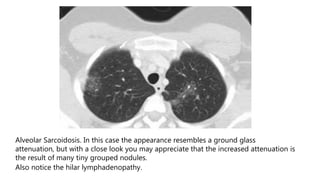

Alveolar Sarcoidosis. In this case the appearance resembles a ground glass

attenuation, but with a close look you may appreciate that the increased attenuation is

the result of many tiny grouped nodules.

Also notice the hilar lymphadenopathy.

The differential diagnosis now includes tumor (bronchoalveolar carcinoma or

lymphoma), eosinophilic pneumonia , organizing pneumonia, Wegener's disease or

an uncommon presentation of sarcoidosis.

There is only one clue to the diagnosis and that is the presence of

small nodules